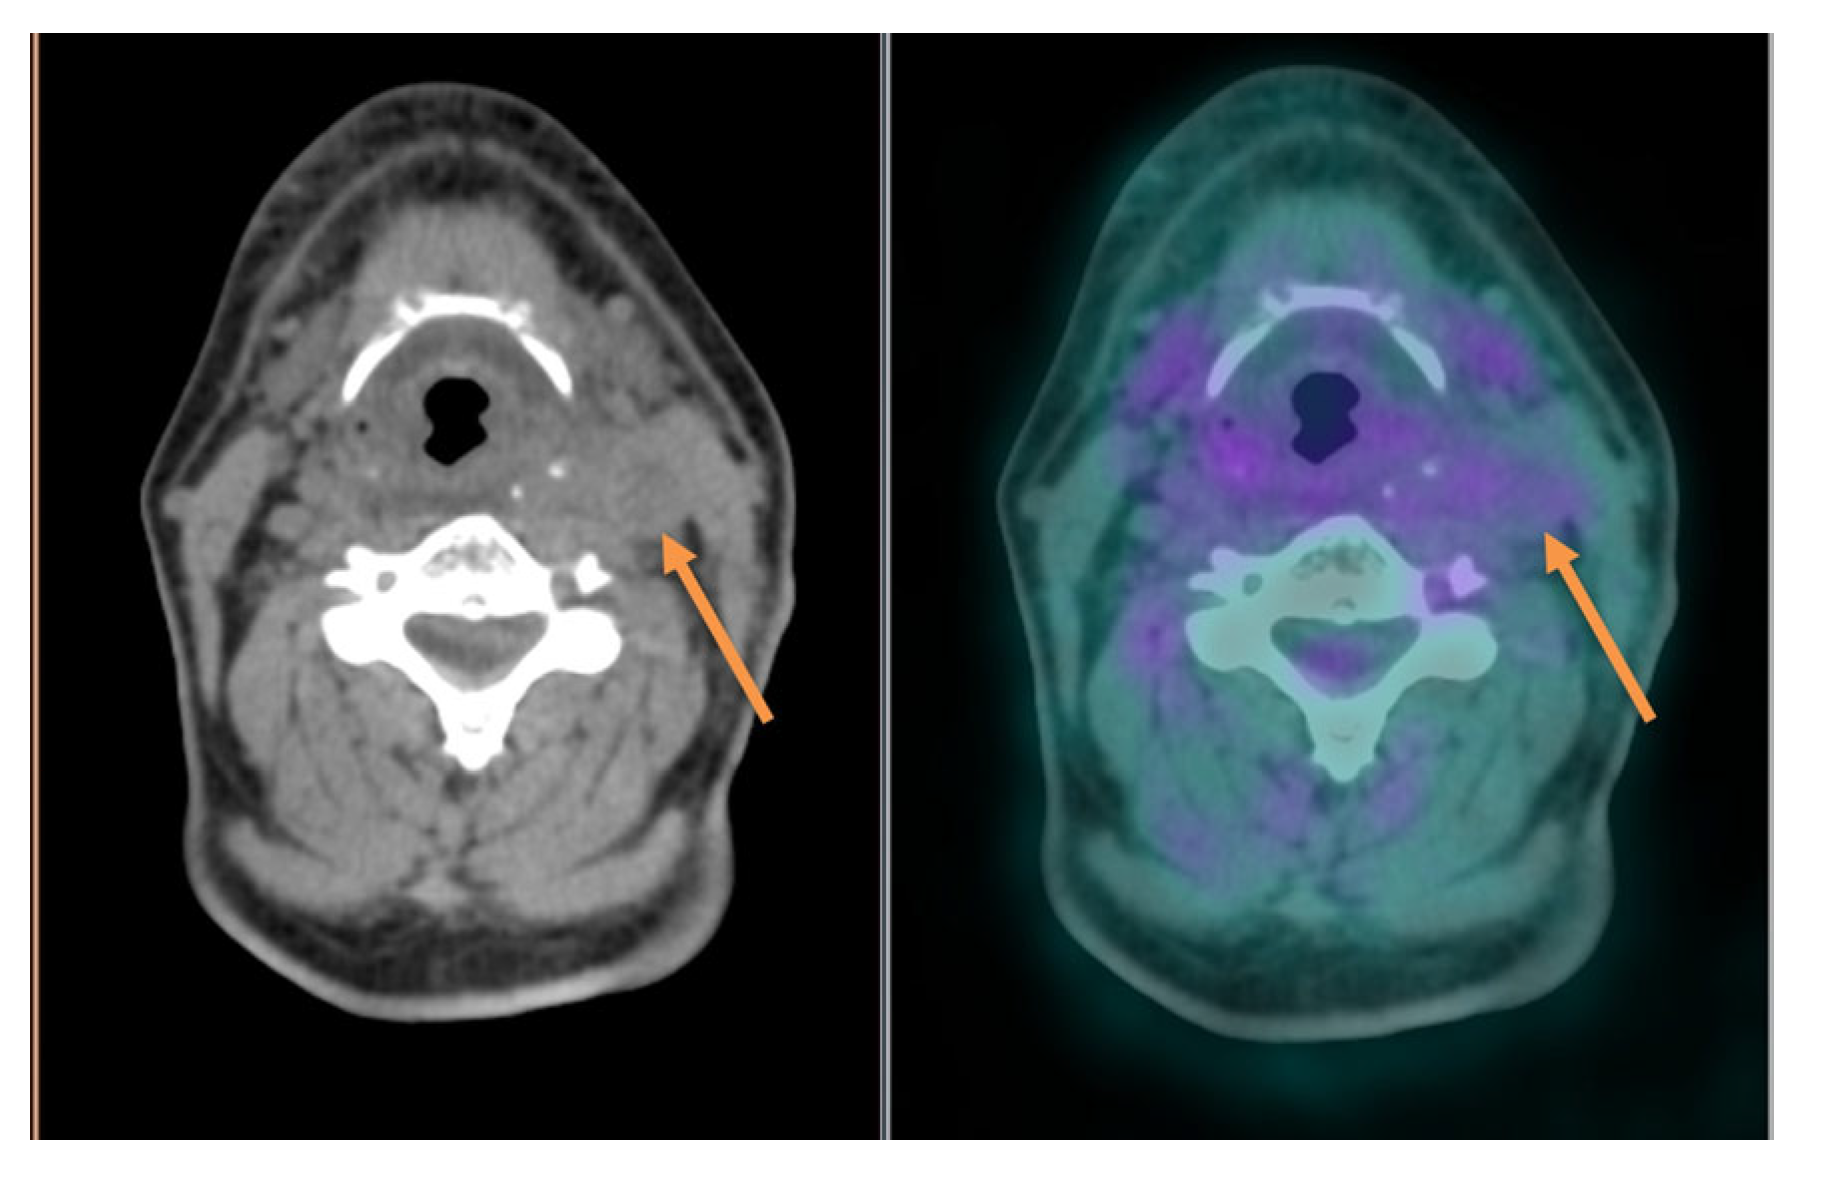

3.2. Cervical Lymph Node Assessment

3.3. Distant Metastasis Assessment

- the high rate of cystic/necrotic neck metastasis with a typical low 18F-FDG uptake [68];